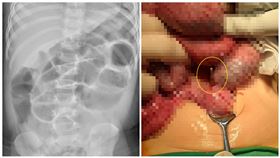

男童嘔吐3天 腸子切開赫見熱門玩具

又有小朋友誤食熱門玩具「巴克球」,中部一名1歲多男童...

2022/07/29 11:28